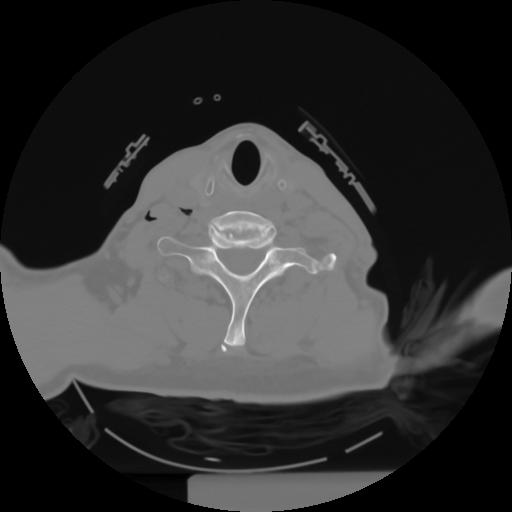

10 P.BLANDAS,,Axial,2.0,P.BLANDAS,,